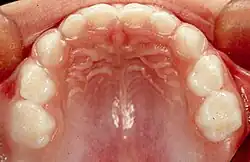

En la dentición temporal hay 20 dientes en total: 8 incisivos, 4 caninos y 8 molares temporales.

Dientes superiores